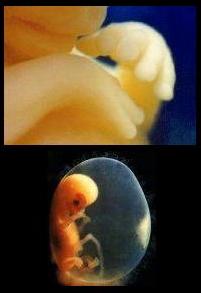

4 haftalık bebek görüntüsü 25 haftalık bebek 25 görüntüsü

anne karnında 4 haftalık

anne karnında 4 haftalık